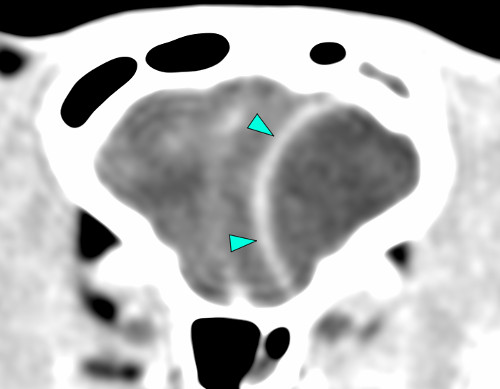

Trois cas résultent de l'extension d'une otite. Ces patients étaient présentés pour ataxie et l'un d'entre eux présentait également des crises convulsives partielles. Dans les trois cas, un examen scanner a mis en évidence une otite moyenne associée à une lésion intracrânienne extra-axiale adjacente, évoquant un empyème méningé. Dans le premier cas, un traitement antibiotique probabiliste permet la résolution des signes cliniques. Dans le deuxième cas, des prélèvements par vidéo-otoscopie permet d'identifier la présence de Staphylococcus felis. Un traitement antibiotique ciblé entraîne la résolution des signes cliniques. Dans le troisième cas, l'examen vidéo-otoscopique permet l'identification de Pseudomonas spp. Malgré une antibiothérapie adaptée, l'état clinique du patient se détériore. Un nouvel examen scanner montre une aggravation de l'empyème méningé. Une craniotomie est réalisée et permet le débridement de l'empyème. Cette intervention, associée à une corticothérapie et la poursuite de l'antibiothérapie, permettent la résolution des signes cliniques.

Nous présentons également un cas d'extension d'une rhino-sinusite infectieuse chez un chat présentant une ataxie. Un scanner montre des lésions naso-sinusales agressives avec lyse de la paroi sinusale frontale et empyème méningé adjacent. Une trépanation du sinus frontal permet de réaliser des prélèvements pour analyses bactériologiques et mycologiques. Un traitement antibiotique ciblé permet une bonne évolution clinique.

Le dernier cas de notre étude est un chat présenté pour ataxie et dont le scanner montre une fracture ponctiforme de l'os pariétal gauche du crâne avec abcès intracrânien et sous-cutané, probablement secondaires à un traumatisme. Un traitement médical est mis en place. Après une amélioration transitoire de son état général, le patient décède trois jours plus tard.

De ce fait, les examens d'imagerie en coupes sont essentiels pour diagnostiquer les abcès intracrâniens. Nous rapportons leur aspect au scanner mais détaillons également leurs caractéristiques à l'examen d'IRM.